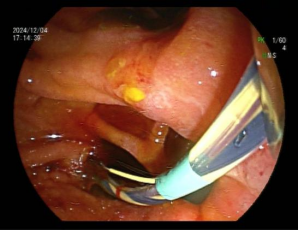

近日,李老先生因“持续性腹痛2月”来我院消化内科二区就诊,期间曾有寒战和发热、黄疸在院外考虑胆总管结石,现为进一步治疗来诊。入院完善腹部MRI+MRCP检查显示胆总管多发结石,结石大小不等,最大直径约1.0cm,胆总管明显扩张。消化二区负责人黄华丽博士完善超声胃镜检查进一步确认了胆总管结石的存在及数量,并发现十二指肠降部多发憩室,十二指肠乳头藏在憩室间,难以发现,这使得常规的内镜逆行胰胆管造影(ERCP)插管变得异常困难(见图1)。

图1十二指肠降部多发憩室,乳头偏歪在憩室边上